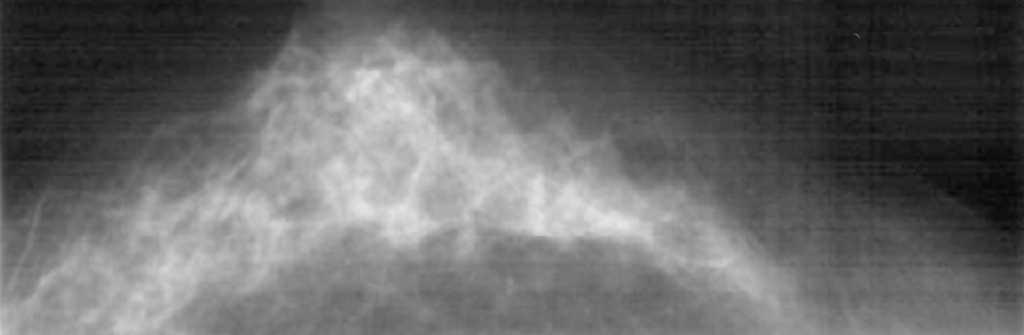

Ante la sospecha de neoplasia mamaria en MD se solicita la realización de una mamografía, ecografía y RM bilaterales. La mamografía muestra unas mamas con tejido fibroglandular de predominio denso con un nódulo espiculado de aproximadamente 1 cm en la LICS de MD. No se aprecian lesiones en MI (fig. 1). La ecografía bilateral confirma la presencia de un nódulo sólido de 1 cm con bordes irregulares, que coincide con la tumoración palpable en la LICS de MD. El estudio de MI no presenta hallazgos significativos (fig. 2). La RM bilateral informa de «... lesión nodular espiculada en LICS de MD con patrón de captación sugestivo de malignidad y que se extiende caudalmente a través de la línea intercuadrántica en presencia de pequeños nódulos satélites con patrones de captación similares que se aproximan hacia el pezón». La lesión nodular principal alcanza unos 14 mm de diámetro mayor, mientras que el conjunto de las lesiones satélites alcanzan unos 15 mm. En MI, «... captaciones significativas en fase arterial con presencia de un pequeño nódulo mal delimitado con un patrón de captación sugestivo de malignidad y con pequeñas lesiones satélite que se extienden caudalmente al igual que en la MD». Estas lesiones están en el cuadrante inferoexterno (CIE), en proximidad de la línea intercuadrántica inferior, a unos 2,5 cm del pezón (fig. 3). Ante el hallazgo de un área sospechosa en la RM de MI se decide solicitar una mamografía magnificada de cuadrantes inferiores de MI, que es informada como normal (fig. 4). Se decide biopsiar con aguja gruesa la masa de MD, y el resultado es de carcinoma ductal infiltrante (CDI) de grado 2.

Figura 3. Resonancia magnética bilateral. Se aprecia una lesión nodular espiculada en línea intercuadrántica (LIC) superior de la mama derecha con patrón de captación sugestivo de malignidad, y que se extiende caudalmente a través de la LIC inferior en presencia de pequeños nódulos satélite con patrones de captación similares (flecha). La lesión nodular principal alcanza unos 14 mm de diámetro mayor, mientras que el conjunto de las lesiones satélite alcanzan unos 15 mm. En la mama izquierda se aprecian captaciones significativas en fase arterial, en presencia de un pequeño nódulo mal delimitado, con un patrón de captación sugestivo de malignidad y varias lesiones satélite que se extienden caudalmente al igual que en la mama derecha. Estas lesiones están en el cuadrante inferoexterno en proximidad de la LIC inferior, a unos 2,5 cm del pezón (flecha).